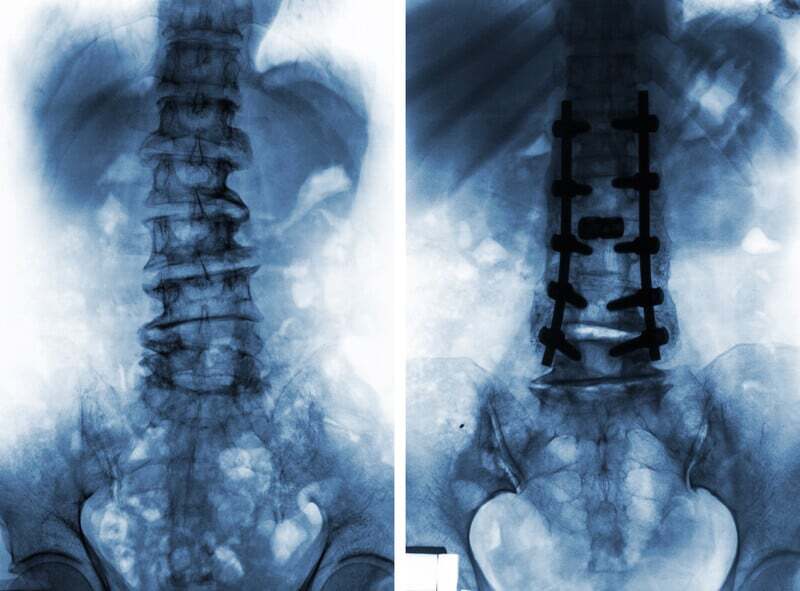

In our practice we often see patients who are in severe back pain. Many have already been recommended to some type of fusion surgery. Their fusion surgery recommendation may be based on pain and it may be based on an MRI image that while showing degenerative changes in the spine, may not be showing what is the cause of the person’s pain.

These people, therefore, may have an MRI, X-ray and/or scan that may show an inaccurate picture of what is causing their pain. What do I mean by inaccurate picture?

The initial enthusiasm about new surgical methods including lumbar spinal fusion was followed by certain concerns about their clinical usefulness and their results.

“(Spinal) Fusion is one of the most commonly performed spinal procedures, indicated for a wide range of spinal problems. Elimination of motion though results in accelerated degeneration of the adjacent level, known as adjacent level disease. Motion preservation surgical methods were developed in order to overcome this complication. These methods include total disc replacement, laminoplasty, interspinous implants and dynamic posterior stabilization systems. The initial enthusiasm about these methods was followed by certain concerns about their clinical usefulness and their results.”